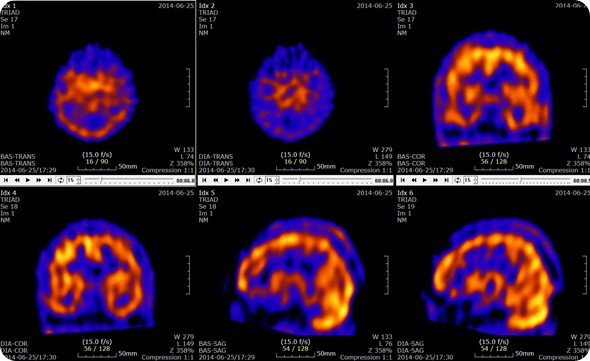

Brain SPECT with Acetazolamide Slices

Brain SPECT with Acetazolamide Slices. Credit: U2em, shared under licenses Creative Commons Attribution-Share Alike 3.0 Unported

SPECT scans are used to determine which parts of the brain are affected by various disorders including Dementia, Epilepsy and head injuries. These are characterized by too much activity in a particular area, too little activity in particular areas or asymmetrical activity across the brain where the activity should be symmetrical. These are all determined through the comparison of the scan results to the standard normal brain scans.

The flow of blood in specific areas of the brain changes as seizures begin. The change in the blood flow can be quantified on the SPECT scan, through an investigation of the differences between a scan taken before a seizure and during a seizure. This change in blood flow can be used to identify the focus of the seizures.